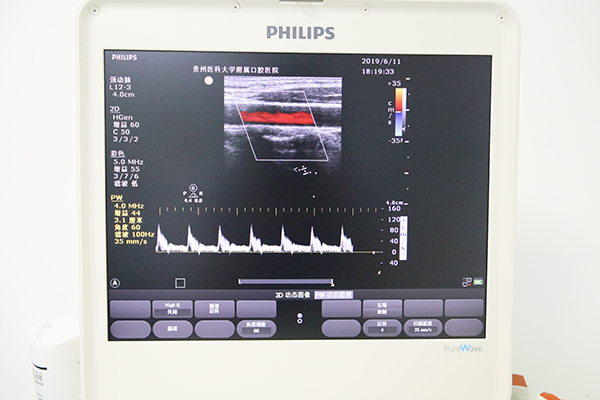

医院配备有业内高端的飞利浦CX-50便携式彩色超声诊断仪设备及图文工作站,为各科室提供全身各系统的超声诊断及超声引导下穿刺,为危重患者提供床旁超声检查服务。目前主要开展的业务范围包括头颈部、浅表器官及软组织、心脏、血管等多个系统的超声检查,可通过经体表超声诊断、超声导向穿刺等方法进行诊断和治疗,具体范围如下:

1、大血管(四肢血管、颈部血管);

2、体表小器官及软组织:甲状腺、乳腺、各腺体、皮肤及皮下包块、外周血管及周围淋巴结等;

3、各组织器官超声引导下穿刺等;

4、心脏超声心动图及心功能评价;

5、危重患者床旁超声检查。